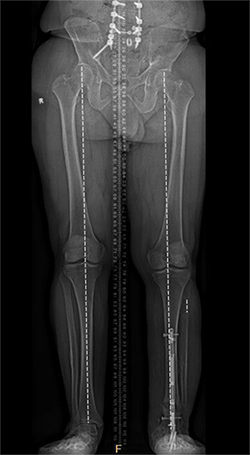

The operation took place in November 2022. Because Natale’s ankle was fused, Marecek chose to lengthen Natale’s tibia, or shin bone, rather than his femur. Marecek also identified that Natale’s ankle had been fused out of alignment. So, first he corrected the ankle’s alignment, then he broke Natale’s tibia and inserted a distraction rod—the kind that could push the two sides of the broken bone apart.

The amount of time the process takes depends on the amount of lengthening and whether more than one limb is involved. Since the rods are not weight bearing, sometimes legs are lengthened separately, which increases the overall time it takes.

Natale says he had to do a lot of physical therapy, stretching the muscles to make space for the longer leg bone. It was about six months before Marecek gave him the go-ahead to put his full weight on it. Even after a year, X-rays showed the bone still hadn’t completely filled in the gap around the rod in his tibia.